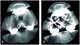

Medial dislocation of femoral component of total hip arthroplasty

Hip replacement is a surgical procedure in which the hip joint is replaced by a prosthetic implant, that is, a hip prosthesis. Hip replacement surgery can be performed as a total replacement or a hemi (half) replacement. [Source: Wikipedia ]